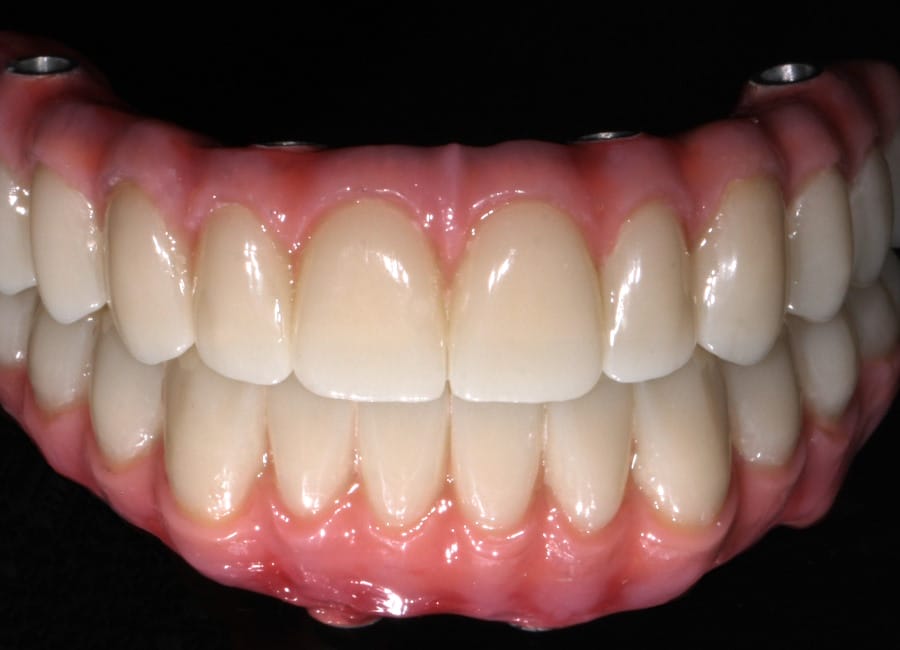

All data were transferred into digital treatment planning software, allowing virtual placement of implants and collaboration with the dental laboratory before surgery. This enabled careful evaluation of long-term outcomes and ensured the design of provisional and final prosthetics could be completed with precision. Following these discussions, the decision was made to proceed with the Fixed-Teeth-in-a-Day approach using the All-on-4 technique.

Surgical phase